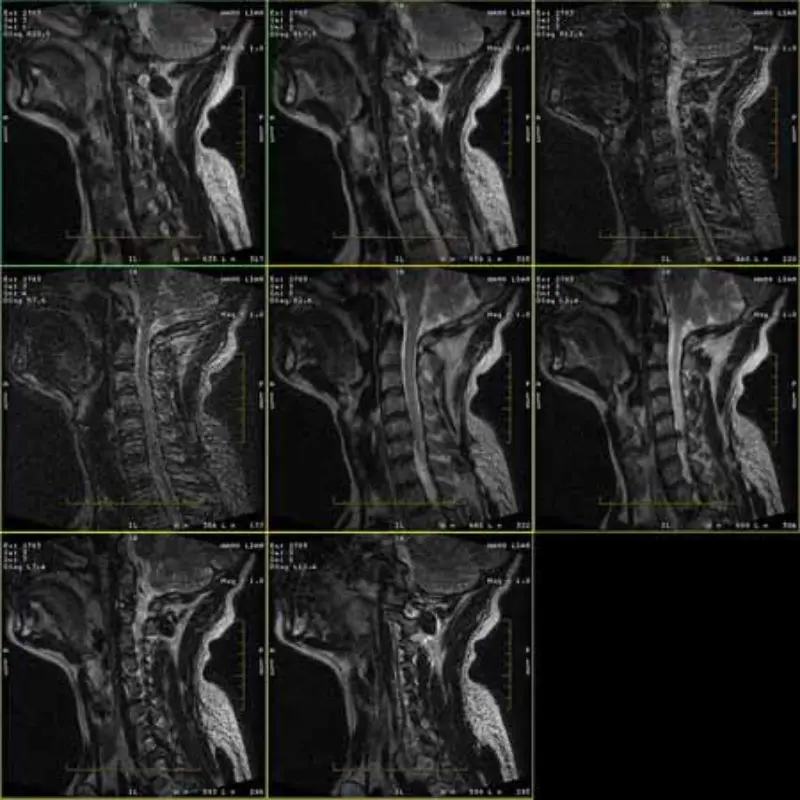

FRFSE および GRE プロトコルの画像にはゴーストがあり、1 つのシリーズに低い SNR の画像が表示されることがあります。ただし、SE プロトコルのイメージは正常です。

画像を添付してご覧ください。